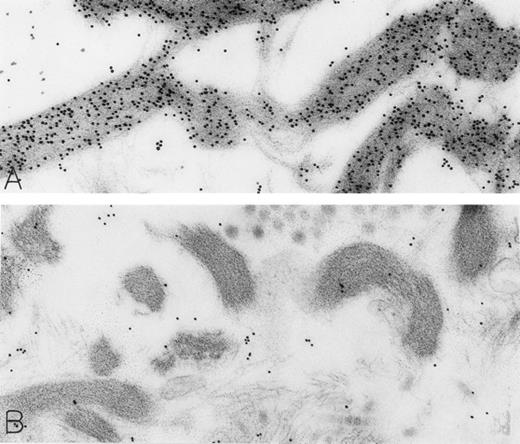

A skin biopsy from an rhSCF-injected test site (obtained 1 hour 40 minutes after the SC injection of 25 μg/kg of rhSCF ) from patient no. 3, who had received a single dose of rhSCF (day 1 of dosing), shows extensive DAO-gold-labeled fibrin (A) that is not seen if the section was digested with DAO before staining with DAO-gold (B). Original magnifications: (A) ×56,000; and (B) ×52,000.

Skin biopsies of rhSCF-injected test sites from patients who had received rhSCF for 1 day (A; obtained 1 hour 40 minutes after the SC injection of 5 μg/kg of rhSCF in patient no. 2) or 6 days (B; obtained 2.5 hours after the SC injection of 25 μg/kg of rhSCF in patient no. 3) show DAO-gold staining of collagen (A) that is largely abrogated by absorption of the DAO-gold with histamine before staining (B). Original magnifications (A) ×31,000; and (B) ×38,500.

The rhSCF-injected skin sites had extensive deposits of extracellular fibrin. Much of this fibrin was bound to interstitial collagen, whereas some fibrin deposits occurred near secretory mast cells and their extruded granules. There was striking labeling of these masses of interstitial fibrin with DAO-gold (Figs 2D and 4A). By contrast, no fibrin was detectable in the control skin biopsies. Specificity controls for the enzyme-affinity method for histamine resulted in no labeling of fibrin (Fig 4B). Bundles of extracellular interstitial collagen in rhSCF-injected sites also stained with the DAO-gold reagent (Fig 5A). Again, specificity controls resulted in no labeling of the collagen at such sites (Fig 4B). In many areas, secretory mast cells, with DAO-gold-negative, extruded, membrane-free granules attached to their surfaces, were intimately associated with gold-labeled collagen fibrils (Fig 2A). However, collagen in the basal lamina (whether present beneath the basal layer of the epidermis and skin adnexae, surrounding Schwann cells in dermal nerves, or underlying vascular endothelial cells and pericytes) did not stain with the DAO-gold enzyme-affinity method (data not shown).